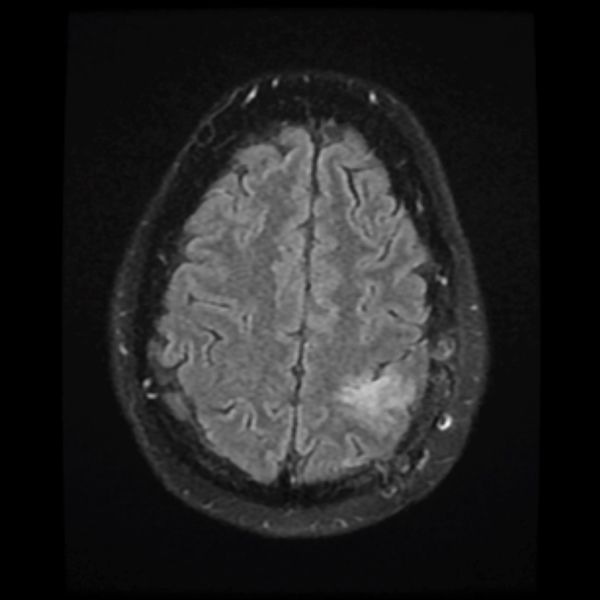

December 2019

Treatment with chemotherapy and radiation under the care of Dr. Grewal resulted in a durable response of the tumor as evident in the post-treatment images.

Neurocognitive assessment by NSPC neuropsychologist Gad Klein, Ph.D., was incorporated into the patient’s care. One month following the initiation of chemotherapy, the patient experienced a marked improvement in seizure frequency, and two months later, he became completely seizure-free. He has now been tapered off seizure medications.

The patient has returned to work with a resolution of cognitive impairment, has no neurological impairment, and the tumor continues to shrink on each serial MRI.